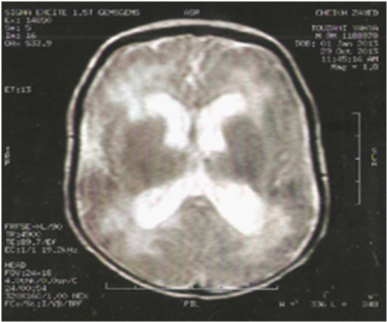

It was a 2 month old admitted to our department for hydrocephalus and brain calcifications. Following a well-attended term pregnancy of non-consanguineous parents. The mother was aged 25 years without significant history. Maternal serologies (toxoplasmosis, mumps, rubella, syphilis, hepatitis B, C) were negative. Morphological antenatal ultrasound was demonstrated, moreover, a triventricular hydrocephalus and diffuse cerebral calcifications. Childbirth was normal. Birth weight was 2770g, with a size of 50cm and a head circumference HC of 36.5 cm. The patient had consulted 15days of life; transfontanellar ultrasound had objectified triventricular hydrocephalus with periventricular calcifications. A brain magnetic resonance imaging MRI revealed calcifications in the white matter and active triventricular hydrocephalus (Figure 1). On admission, the newborn was pink toned, responsive and a febrile, the weight was 4300g (-1 SD), the size of 55Ccm (normal), with a PC to 41cm (+2 SD). Neurological examination noted axial hypotonia. The remainder of the physical examination was unremarkable. Biologically, there was an inflammatory syndrome with increased C-reactive protein (CRP) plasma at 47mg/L, normochromic - normocytic anemia, a hemoglobin concentration of 9g/dL and ferritin increased to 600mcg/L, white blood cells and 10054/mm3 to a normal platelet count. Renal and hepatic functions were correct. Cytomegalovirus, rubella and toxoplasmosis serology were negative. Polymerase Chain Reaction PCR CMV was positive (3000 copies/105 L). Antiviral treatment had proposed by ganciclovir 10mg/kg/24h for 6weeks, we obtained a good outcome. Neurological monitoring (electroencephalogram EEG, evoked auditory and visual) and hematological outcome 3 months later was averted complications medium term. The patient had an external ventricular drainage (EVD) at 6 months. The evolution was favorable.

Figure 1 MRI brain: Triventricular expansion with periventricular lesions.